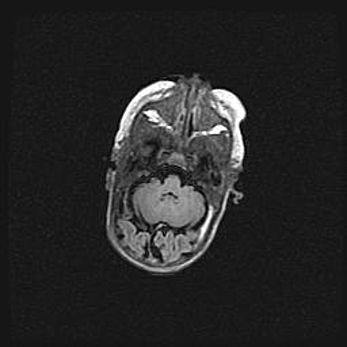

Подострая гематома правой гемисферы мозжечка.

Наружная гидроцефалия.

Возраст: 15 дней

Вес: 3100 г

Пол: женский

Окружность головы: 37 см

Срок гестации: 35-36 недель

При открытой наружной форме гидроцефалии у новорожденных расширяются и переполняются субарахноидные пространства.

Кровоизлияния в мозжечок имеют две клинико-анатомические формы: полушарные гематомы и кровоизлияния в червь.

К появлению этой патологии может привести: повреждения головного мозга, возникающие в результате асфиксии и гипоксии плода при беременности, или травмы во время родов. Редко гематома мозжечка может быть результатом первичной коагулопатии и сосудистой мальформации, диссеминированном внутрисосудистом свертывании, изоиммунной тромбоцитопении.